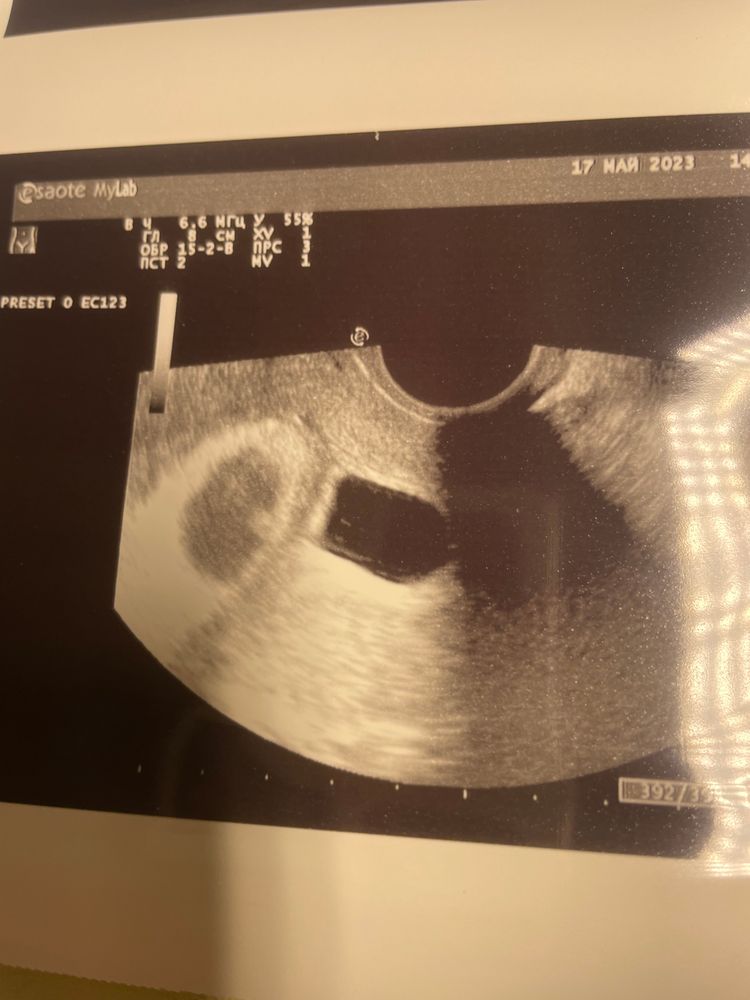

عائشة, здравствуйте. Сделала платное узи. Это чёрное пятно на новом узи вообще отсутствует. Плод один. Все ок. Гематома застарелая. Говорит прекрати паниковать. Все нормально.

Мария, мне кажется это не ПЯ.но я не врач. у меня так гематома (отслойка) выглядела на 5-6 неделях

Евгения, я тоже неделю лежала. У меня отслойка была 1,5 см на 8 мм, а пя 1.7 см. Они сейчас пишут что есть гематома какая то краевая 1.2 см на 6 мм. А это типо яйцо второе. Но как это может быть второе яйцо? На 1 узи мне померили сердцебиение 109. Тут ставят мне просто сердцебиение +. Сколько ударов не ставят. Я вообще вся на нервах.

Евгения, мне два дня тоже кололи внутривенно. потом перевели на таблетки. Сегодня узи и вот это. А выделений не было вообще с кровью или с примесью. Покалывало бывало живот. Потом я пошла узи установить факт беременности и мне написали в заключении: деформация плодного яйца, рхг 1,5 на 0.8 мм. Частичная отслойка. Положили в больницу. Итог на фото узи.

Всё ли видно на УЗИ? Нельзя исключить замершую беременность